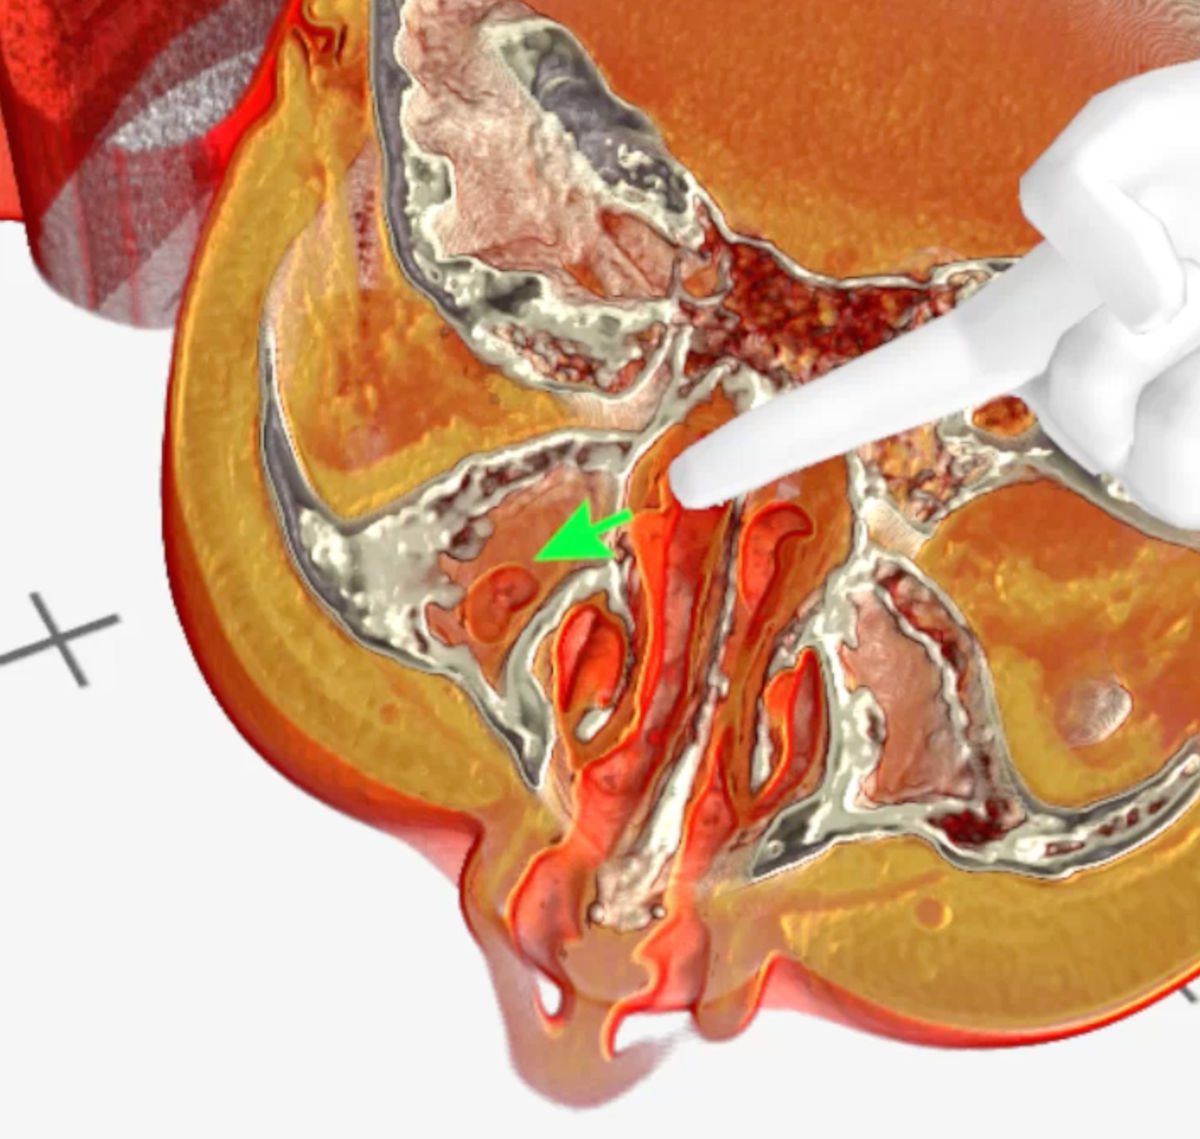

These lesions were visualized with volumetric 3D-rendering of the CT and MRI images with Medical Imaging XR software (MedicalHolodeck, Switzerland), which allowed for better evaluation of the pathologically altered craniofacial anatomy (Fig. 6-9).

Figure 6. Medical Imaging XR 3D-rendered CT shows residual aeration of the right maxillary sinus (green arrow).

Figure 7. Medical Imaging XR 3D-rendered CT shows bone destruction of the left maxillary sinus walls..